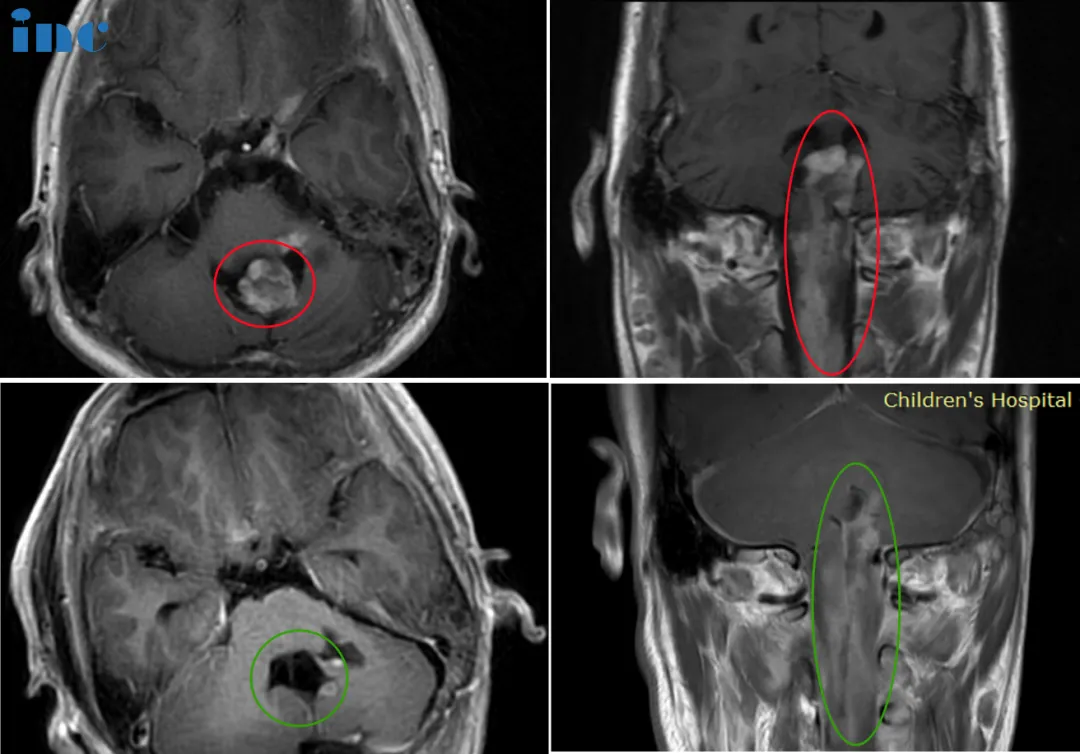

14岁男孩-脊髓髓内节细胞胶质瘤

14岁的睿睿2016年底偶发左手抓握力弱,2017年初查出神经节细胞瘤;医生表示肿瘤生长缓慢,无法全切,还会复发,故保守观察。2021年底,双侧肢体无力加重,左侧更明显。2022年睿睿再次就医检查,肿瘤位于脑干延申至脊髓,肿瘤占位大小33*42*94mm。在国内某医院做了一次开颅手术,虽仍有不少残留,但手术取得完整病理,肿瘤导致的病情有适当好转,为后续手术提供了清晰的思路、争取了时间……

▼巴教授术前术后影像对比

“是的,男孩可以接受手术,而且,为了生存,这是他的机会。如果不做手术的话,由于肿瘤的进展,尽管已经做过气管造口术,男孩会出现很严重的吸入性肺炎和逐渐恶化的四肢麻痹。因此,应该给他生存的机会,幸运的话临床症状在一定程度上会有好转,尤其肿瘤不是恶性的”

在手术后会残留一些较小的肿瘤部分。对于此,靶向化疗是治疗选择,也许也会有质子治疗的指征,但这是比较晚的时候。对于这种节神经胶质瘤的病人来讲,都存在复发的风险。但另一方面,随着时间的推移,肿瘤的侵袭性将明显地降低,肿瘤再生长的风险也会低很多。甚至后期再次手术也是可行的。

14岁的睿睿首次手术微能全切肿瘤,残余的肿瘤持续的占位压迫效应,睿睿短期内出现了一些不良的症状。此时的睿睿已经无法像同龄的孩子一样学习、生活……抬眉和微笑等动作受限,吞咽功能减弱,第一次手术术后一直保持气管切开和鼻饲状态。巴教授在咨询报告中评估道:

我认为,男孩在术后六到八个月以内能恢复的可能性很大,从而去掉气管插管,吞咽(自主进食)将变的可能。但这不会在手术后很快就发生,男孩的恢复会需要一定的时间。从我来看,根据组织病理的诊断,预后会相当好的。

对于手术的效果,睿睿父亲非常满意,没有戴呼吸机,气管插管拔掉,可自主呼吸。手术一周之后基本就可以自己坐起来,在之前完全无法想象。